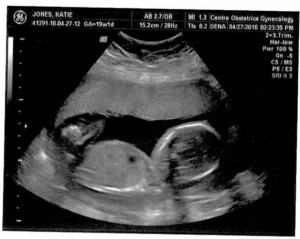

Here are a couple of ultrasound images of little McLain (Mamabea’s maiden name, and the little boy’s handle). He will go by the name McLain, but we still have to decide on his first name.

For the first time since Katie’s been pregnant the second time, she predicted a boy, in a note she sent me this morning. Her prediction was validated with an image at 2:15 p.m. as Sarah, Katie, and I looked at the screen on the wall during an ultrasound. When we checked in with Katie’s OB today, the fetus was 15.2 cm with a 143 bpm heart rate. We’re thrilled of course, although Katie and I agreed last week that we would be every bit as excited for Jackie to have a little sister.